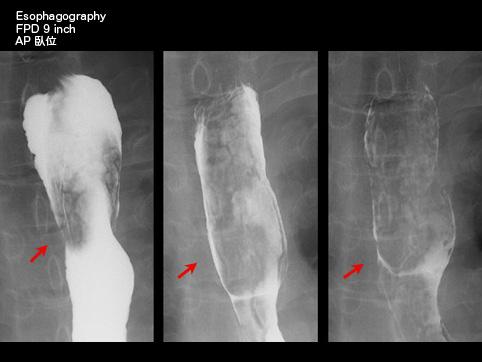

A case of esophageal lipoma in a patient that presented with dysphagia.

Non-epithelial tumors/Lipoma

Esophagus/More than one of the above

X-ray

40 -